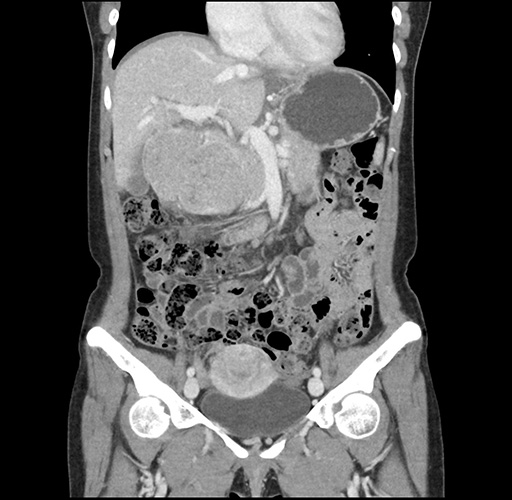

Imaging Analysis

Look through the patient's CT scan to identify any areas of concern for the necessary procedure.

Based on your CT findings, which issue(s) would give reason for "planned slowing down moment(s)" in this case?

Considering a standard left lateral sectionectomy procedure, what step(s) of the operation would you do differently in this case ?